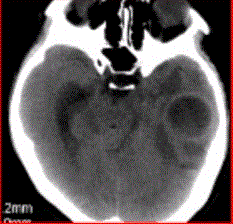

问题 患者女,26岁,头痛、低热10d余,既往有左侧慢性中耳炎病史。CT表现如下图。 脑脓肿的感染途径不包括

选项 A.中耳炎经鼓室盖直接蔓延 B.乳突炎直接蔓延 C.血栓性静脉炎所致 D.血行感染 E.淋巴途径感染

答案 E